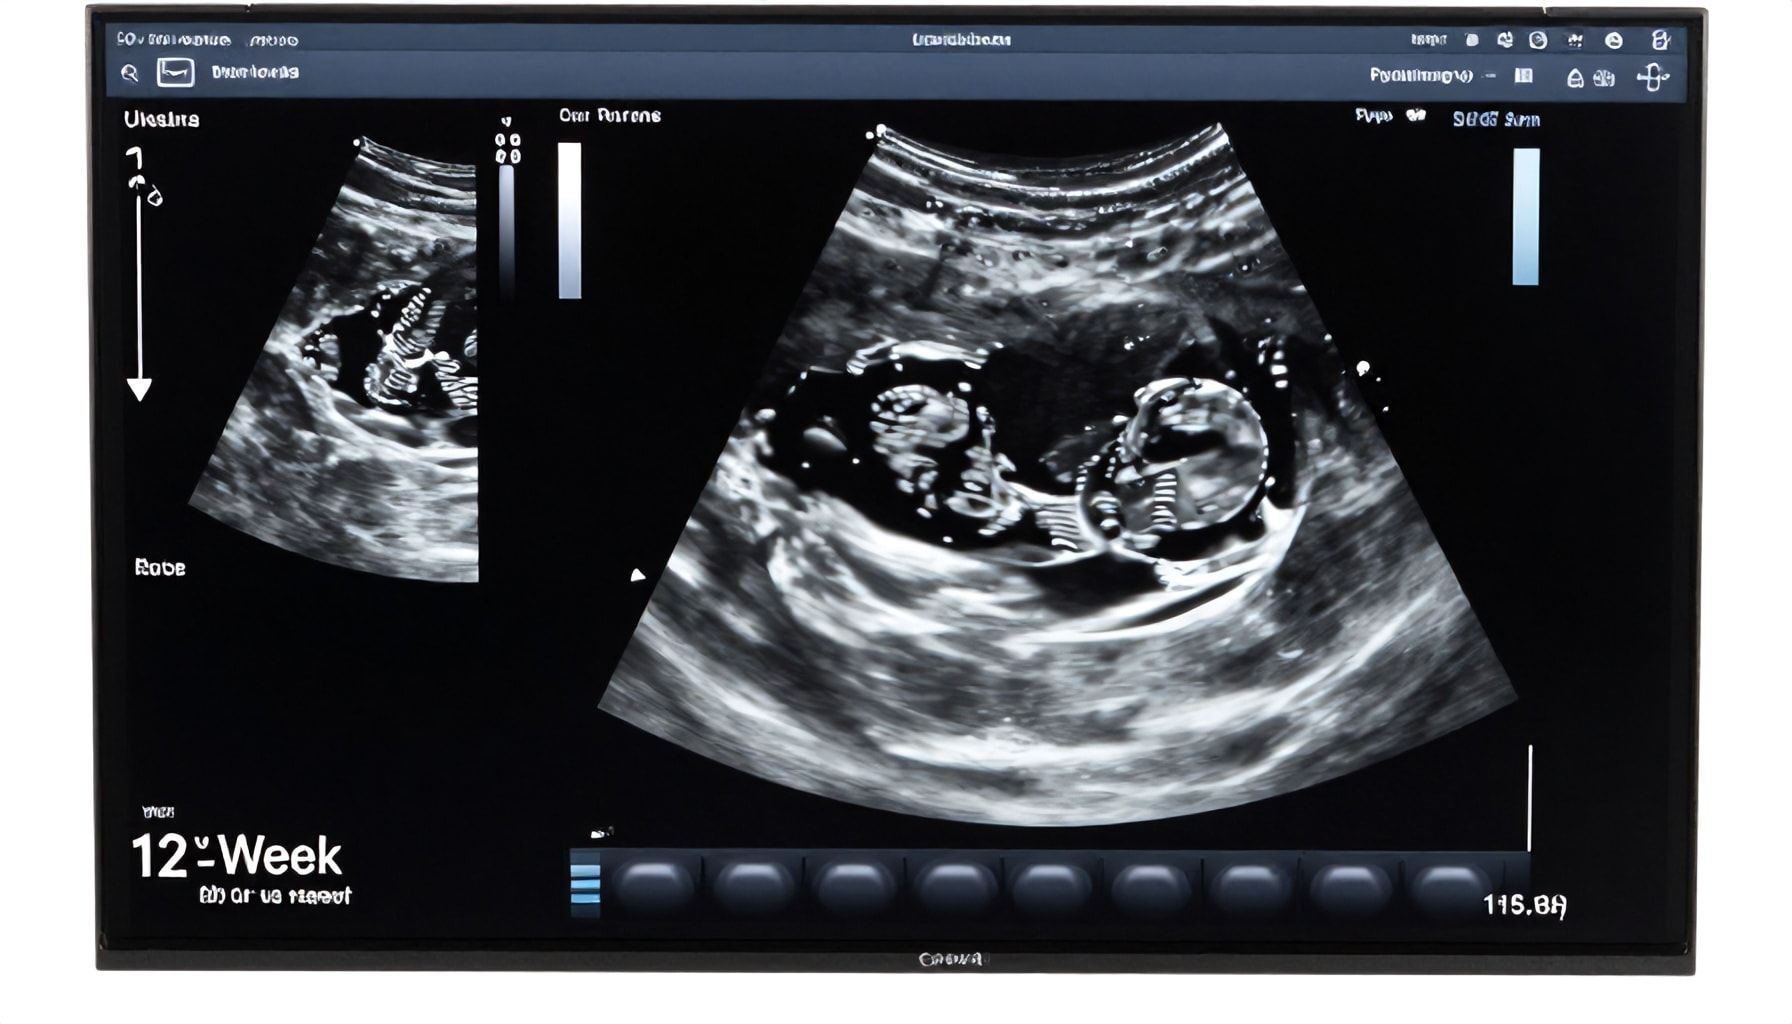

- Crown-rump length (CRL): The tech measures your baby from head to rump—this is the most precise way to date the pregnancy. At 12 weeks, your little one is about 2 inches long, roughly the size of a plum.

- Heartbeat: The heart is pumping at 120-160 beats per minute. You’ll hear it loud and clear, a rhythmic whoosh that’s music to any parent’s ears.

- Nuchal translucency (NT) scan: This is the big one. A thickened fold at the back of the neck can indicate Down syndrome or other chromosomal issues. The measurement is taken in millimeters, and the results are combined with blood tests for a more accurate risk assessment.

- Crown-rump length (CRL): Around 2.1 inches (53 mm). The tech will measure this to date your pregnancy accurately.

- Heart rate: A healthy 120-160 beats per minute. If it’s too fast or slow, your doctor will monitor closely.

Now, let’s talk practicality. This scan often includes the nuchal translucency screening, a key test for Down syndrome and other chromosomal conditions. A thickness of 2.5 mm or less is typically reassuring, but numbers alone don’t tell the whole story. I’ve seen parents panic over a slightly elevated reading, only to have follow-up tests come back clear. Context matters.